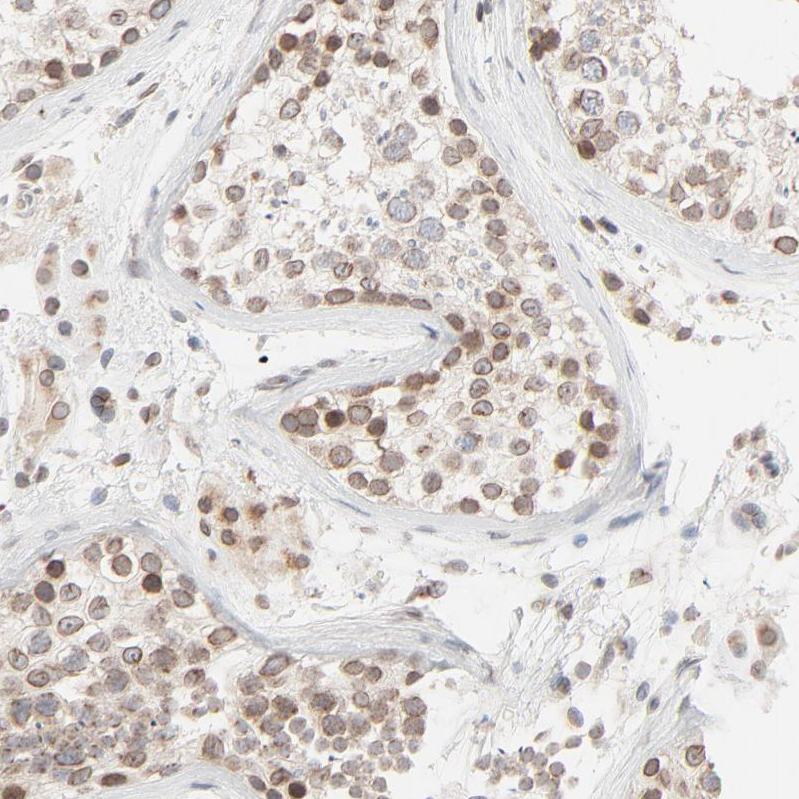

Immunohistochemical staining of human lymph node shows moderate positivity in nuclear membrane in germinal center cells.